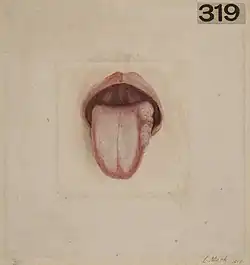

Venous malformations are the type of vascular malformation that involves the veins. They can often extend deeper from their surface appearance, reaching underlying muscle or bone.[12] In the neck they may extend into the lining of the mouth cavity or into the salivary glands.[11] They are the most common of the vascular malformations.[13] A severe venous malformation can involve the lymph vessels as a lymphaticovenous malformation.[11]